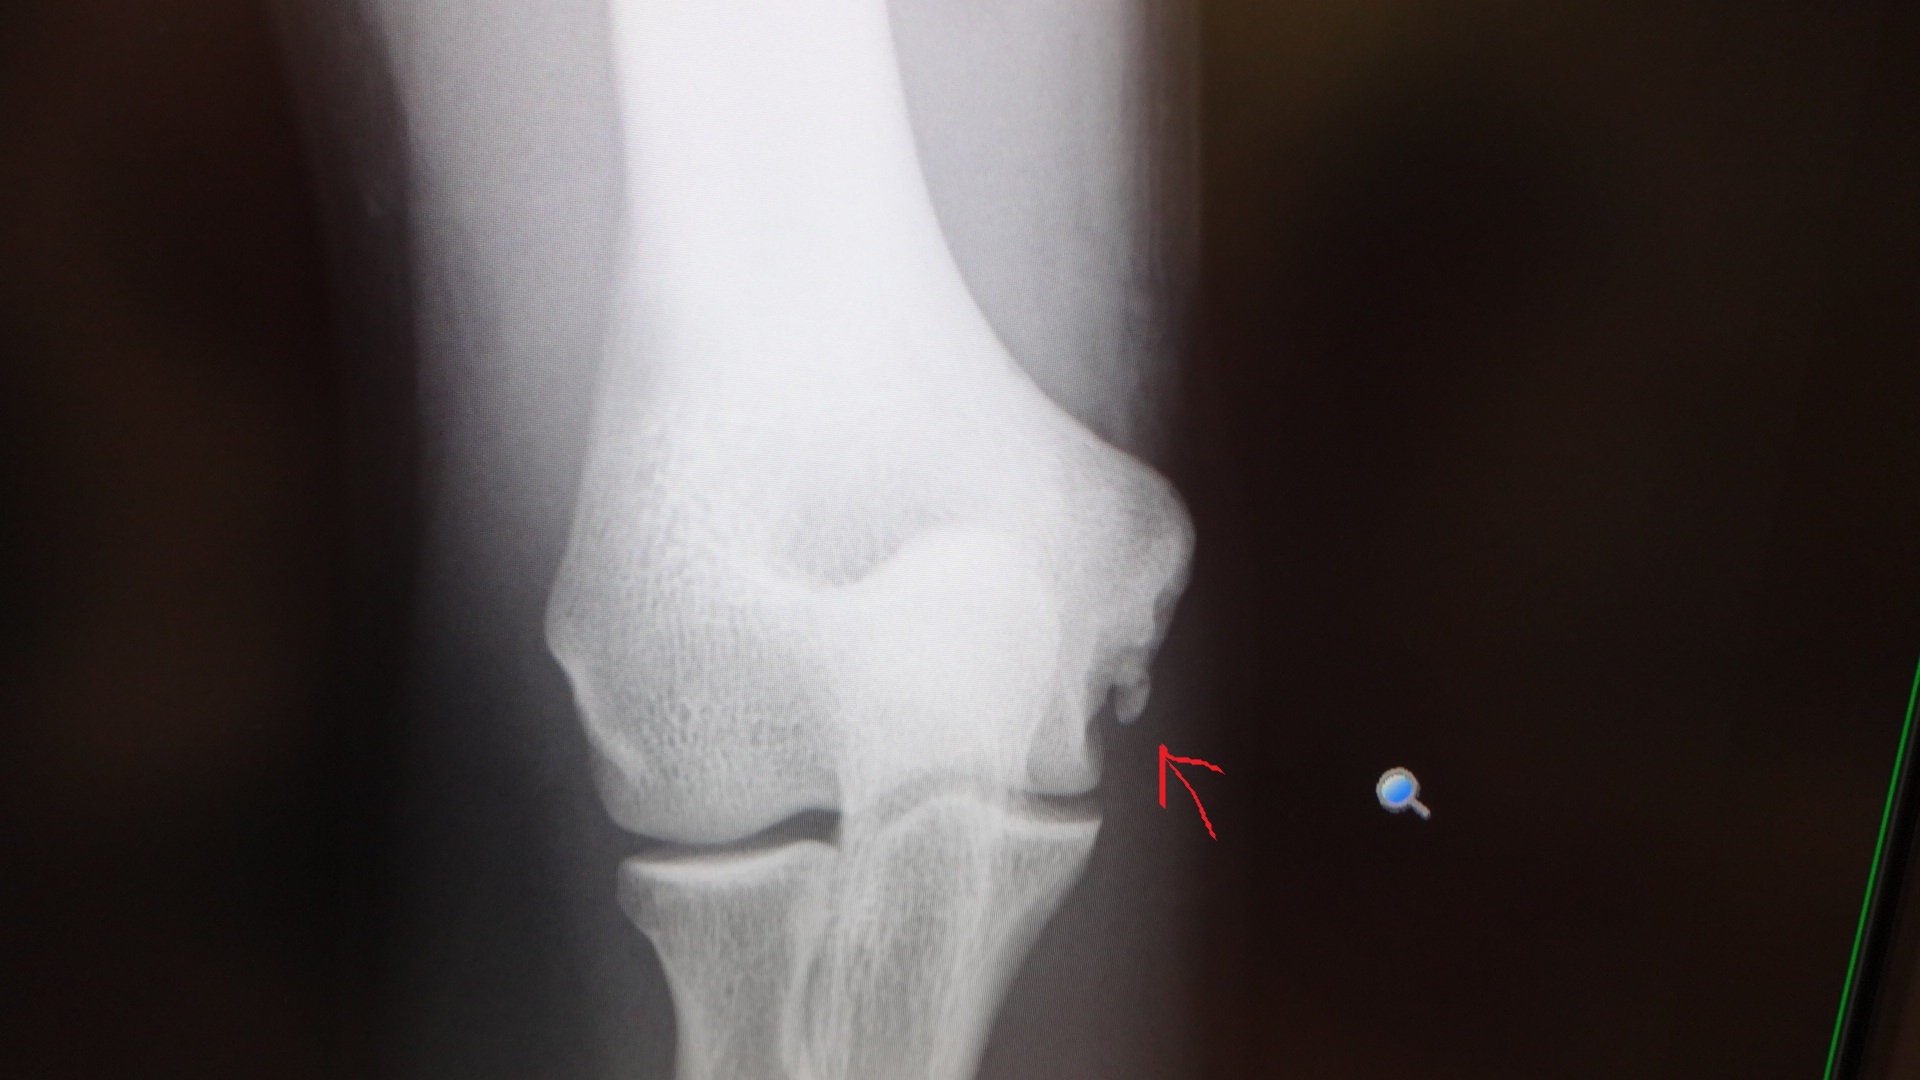

*今回のブログには、肘のレントゲン写真が載っていますので、

苦手な方は、スルーして下さい。

5月の時の肘のレントゲン写真は、

こちら。

矢印の所に、突起物が有ります。

靭帯が切れて、剥がれ掛かっているそうです。

今回の受診で、再度、レントゲンを撮ったのですが、

今回は、

この様になっていました。

突起物も、大きくなっていて、

かなり悪化しているとの事。